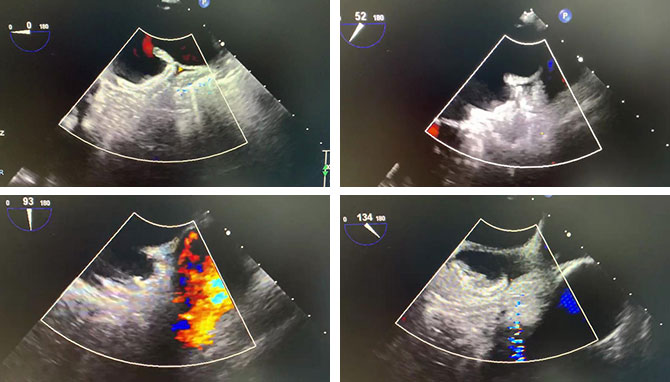

食道超声TEE下观察各角度无残余分流,封堵盘与心耳开口完美贴合